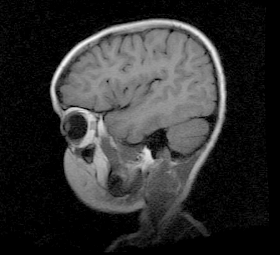

Aux dires de Robert, il semble que ce problème difficilement détectable soit relié au cerveau. Les médecins américains qui ont étudié son cas vont poursuivre leur investigation en présentant ce cas à des collègues aux États-Unis. Ils ont insisté pour que les parents gardent espoir en se confiant à Dieu. Ceci dit, même là-bas, une telle opération s’avère très difficile.

Au bas, vous trouverez le message de Robert Kalindiza tel que je l’ai reçu. Il y a aussi quelques photos, plutôt de mauvaise qualité, qui accompagnent la petite vidéo.

After all the effort we made since January, all the scans and diagnosis and the surgery that my son underwent, American doctors have ruled out that he should not go through any type of surgery. And they said we are lucky that the first surgery was successful but the case of Serge is complicated. The problem starts in the brain but it was very difficult to identify it. But the equipment that they brought from America revealed all the problems.

See above all the photos of his brain and Doctors who tried their best to help Serge.